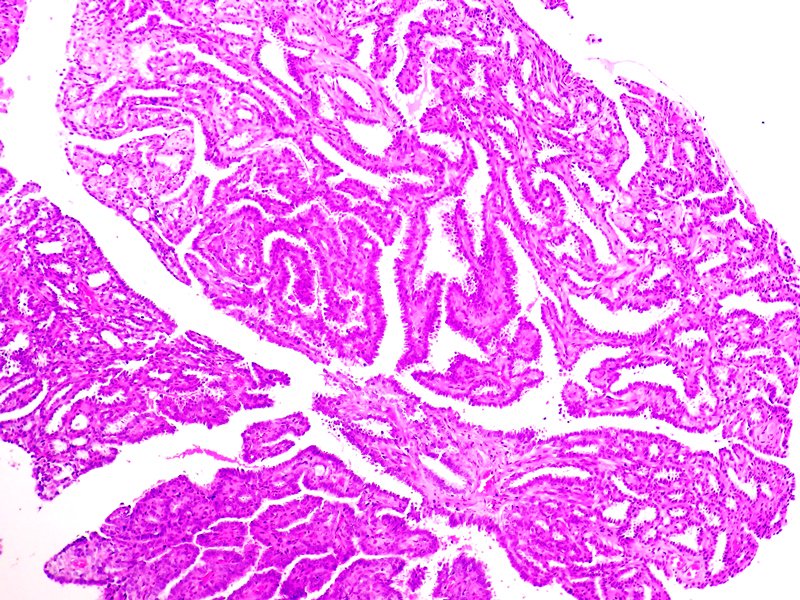

Epidídimo. Cistadenoma papilar. Tinción HE